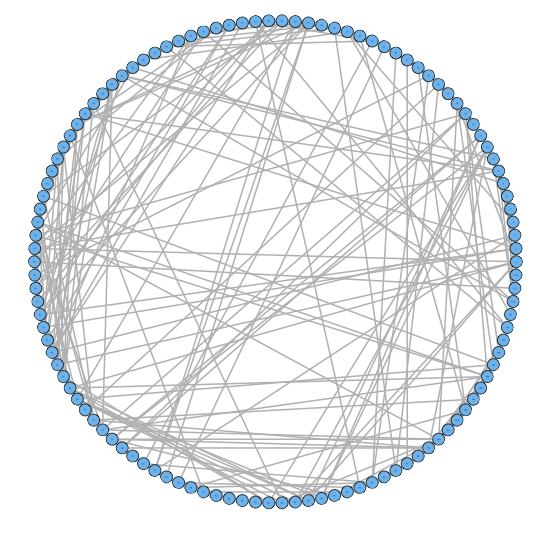

For our two-level problem (1.1.1), we must account for two sources of network variability when conducting population inference: (i) variability between subjects within a group and (ii) variability of the network selection procedure within a single subject. To see this, let us study a real multi-subject fMRI example. In Figure 2, we show estimated functional brain networks for subjects from the UCLA fMRI ABIDE data set INDI (2013). We describe the details of this data set, our pre-processing, and brain parcellation later in the Case Study in Section 5. In the top and middle panels, we estimate brain networks for each subject using graph selection methods for Gaussian graphical models (see Section 3.1 for details) and plot these as circle graphs to easily visualize network differences. It is clear that there are not only differences between autistic subjects and control subjects, but there is also large heterogeneity across subjects within each group. This is well-known in the neuroimaging literature (Milham et al., 2012; Nielsen et al., 2013), and makes finding statistically significant differences between subject groups much more challenging.

Less well studied in neuroimaging, is the second source of variability which arises from estimating networks for each subject instead of directly observing the networks. In the bottom panel of Figure 2, we re-estimate brain networks for a single control subject with bootstrap resampled data. It is clear that there is major intra-subject variability arising from our graph selection procedure. Indeed in neuroimaging, test–re-test studies which conduct brain imaging on the same subject in repeated sessions have shown high variability in the subject’s estimated brain networks (Wang et al., 2011). This also motivates the necessity of using a two-level model like (1.1.1) for population network inference as opposed to the one-level model and test statistics of the standard procedure.